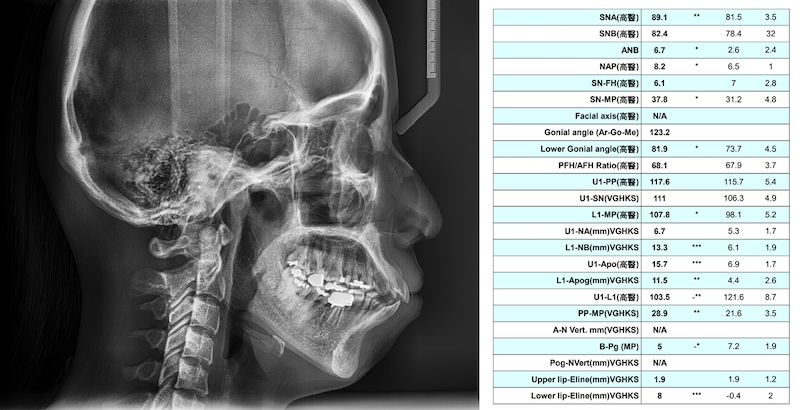

有時候外觀上無法判別的部分,會經由側顱X光片(Cepha)分析數據,以便醫師下更精準的判斷。通常矯正專科醫師會拍攝這張X光進行骨性的分析,其中包含了數十種角度和線段,今天先帶大家看看最簡單的量測點AB點,可以分別去定位出上顎骨和下顎骨過多的量(與正常人的平均數值相比)。

骨性暴牙範例:

從下面的側顱X光數值分析表可以發現:A點(SNA)相對於正常值多出7點多度,B點(SNB)靠近正常值,顯示上顎骨暴成分較多,而下顎的暴牙偏齒性較多。